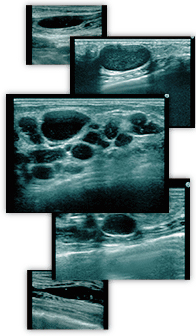

THE CLINICでは、このような他院で受けたヒアルロン酸注入の豊胸によるしこりのお悩みに対応すべく、乳腺用エコーを使用し、しこりを目視しながら確実に除去する治療法を採っております。

- エコー診断で確認できること

- しこりの位置

- どこにしこりができているかが明確に分かります。

- しこりの原因

- しこりが何によるものなのかを調べられます。

- しこりの状態

- 大きさや石灰化の有無などを把握できます。